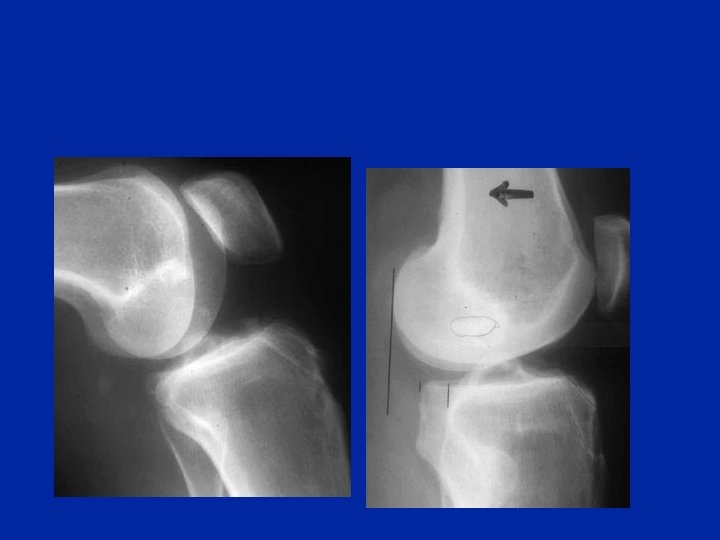

A recher sur les radiographies simple Face et profil La fracture de Segond

A recher sur les radiographies simple Face et profil Arrachement de la tête du péroné

A recher sur les radiographies simple Face et profil IRM Massif des épines tibiales

Lésions associées Massif des épines tibiales Tête du péroné Les radiographies simples de face et de profil sont indispensables pour dépister une fracture associée possible d'un plateau tibial ou d'un condyle. On recherche des images d'arrachement des insertions osseuses des ligaments (interne, externe ou des croisés sur le massif spinal)

Les arrachement de l’insertion osseuse tibiale du LCA Se voient 8 fois sur 10, avant 12 ans Type III Type IV Classification de Meyers et Mc Keever